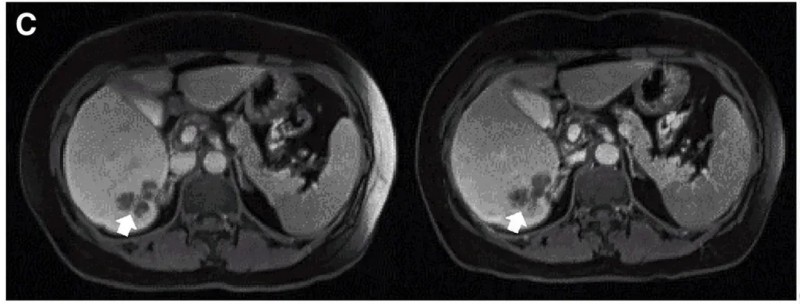

试验数据同样振奋:10例既往治疗进展(PD)的患者中,7例治疗后达到病情稳定(SD),肿瘤直径仅轻微变化,其中2例患者的稳定状态持续超30周(7.5个月)。典型病例的疗效尤为亮眼:P10患者接受DL4剂量治疗后,MRI证实其肝内一处病灶明显缩小(详见下图)。

▼P10患者在CAR-T治疗前(左图)、治疗4周后(右图)的MRI对比

▲图源“Molecular Therapy”,版权归原作者所有,如无意中侵犯了知识产权,请联系我们删除